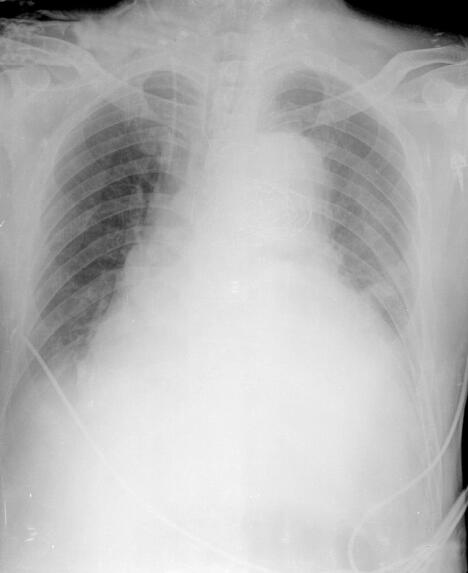

患者补液及调整呼吸参数后血流动力学趋于稳定,血压回升,去甲肾上腺素减量至0~0.05μg/(kg·min)。但低氧血症仍无明显改善。双肺叩诊呈清音,呼吸音对称,双肺底闻及细小水泡音。心率113次/分,心律绝对不齐,各瓣膜听诊区未闻及病理性杂音。腹部膨隆,明显腹胀,叩诊呈鼓音,无肌紧张,肠鸣音未闻及。床旁卧位胸部X线(图1)示:肺容积缩小,肺透光度下降,心影增大,肺门纹理增强,紊乱。疑诊ALI,予定期肺复张及俯卧位通气,效果不佳。

图1